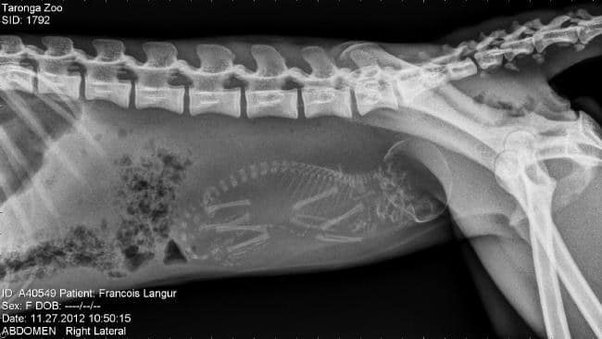

مجموعة من الصور بالأشعة السينية لبعض الحيوانات، معظمها في حالة الحمل.

الصور بالفعل مذهلة، سبحان الله العظيم.

7️⃣ قردة حامل.